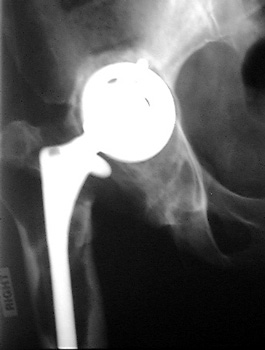

INFECTION—Soft tissue gas.

Gas in neo capsule of right total hip replacement secondary to sinus tract from joint to skin